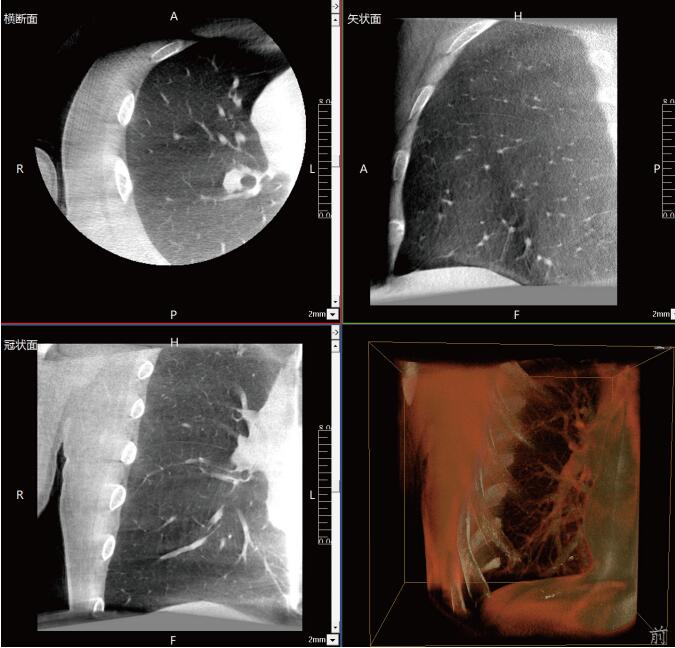

一站式“術(shù)中CT”,肺部診斷+治療新選擇

滿(mǎn)足肺結(jié)節(jié)活檢、肺結(jié)節(jié)切除、肺結(jié)節(jié)消融治療等各類(lèi)術(shù)式的術(shù)中影像要求:

常規(guī)流程下需要術(shù)前CT室內(nèi)的引導(dǎo)定位,再轉(zhuǎn)入手術(shù)室進(jìn)行胸腔鏡手術(shù),在轉(zhuǎn)運(yùn)過(guò)程中有氣胸、肺出血和導(dǎo)針脫落的風(fēng)險(xiǎn)。使用大功率平板三維C形臂PLX C7600,可在手術(shù)室內(nèi)一站式完成肺部三維影像重建,在穩(wěn)定呼吸的條件下,亞亳米級(jí)定位肺結(jié)節(jié)位置,有效規(guī)避穿刺路徑附近的血管、氣管等重要解剖結(jié)構(gòu),術(shù)中確保穿刺安全有效。同時(shí)可大幅降低輻射劑量,減少射線對(duì)醫(yī)患的傷害。